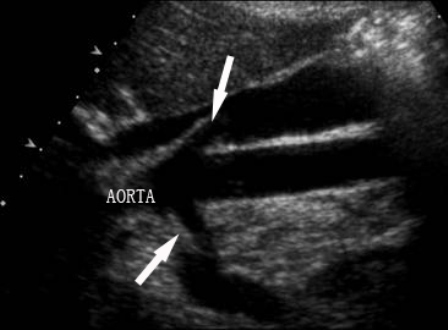

figure_1a